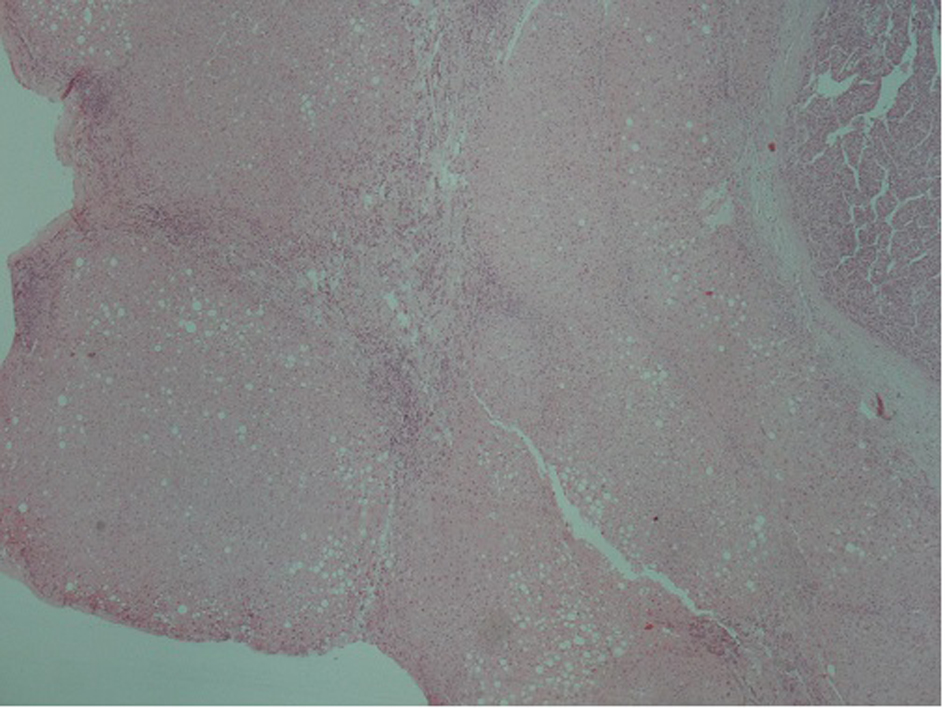

A 51-year-old patient with a history of active hepatitis-B viral infection, psoriatic arthritis, heavy alcohol and tobacco use, was referred to the Oncology Department having been recently diagnosed with metastatic HCC (stage IVB). A sizeable mass had been identified in the right liver lobe (Fig. 1) and bone metastases in the thoracic and lumbar vertebrae. The diagnosis was established by liver biopsy (Fig. 2) and a significantly elevated serum alpha-fetoprotein level (above 2,500 ng/mL reference values below 8 ng/mL). The biopsy was consistent with a poorly differentiated HCC and showed evidence of micronodular cirrhosis (Fig. 3). The patient was palliatively treated with sorafenib (multikinase inhibitor) 400 mg po bid.

![]() Click for large image | Figure 2. Microscopic appearance of hepatocellular carcinoma. Note the trabecular pattern of growth (H&E, × 10). |

![]() Click for large image | Figure 3. Hepatocellular carcinoma (arrow). In the adjacent liver parenchyma incomplete cirrhotic nodules (star) and fatty changes were observed (H&E, × 4). |